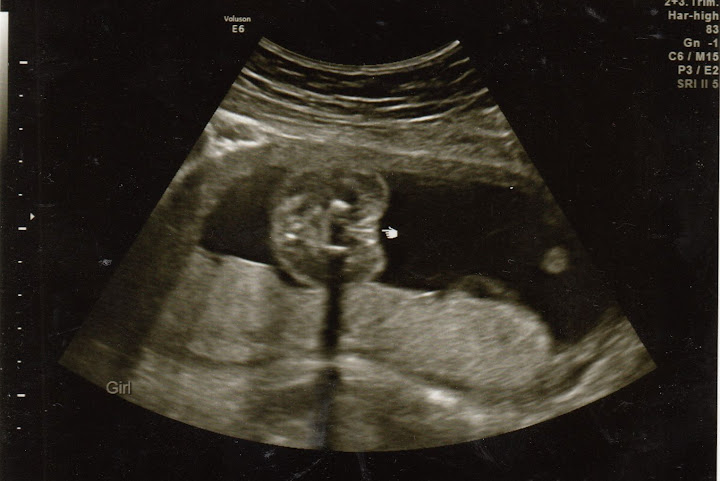

Isn't she cute??? I think she's rubbing her eye in that profile shot. And, yes, we have mostly definitive proof our little kung fu champ is a she: